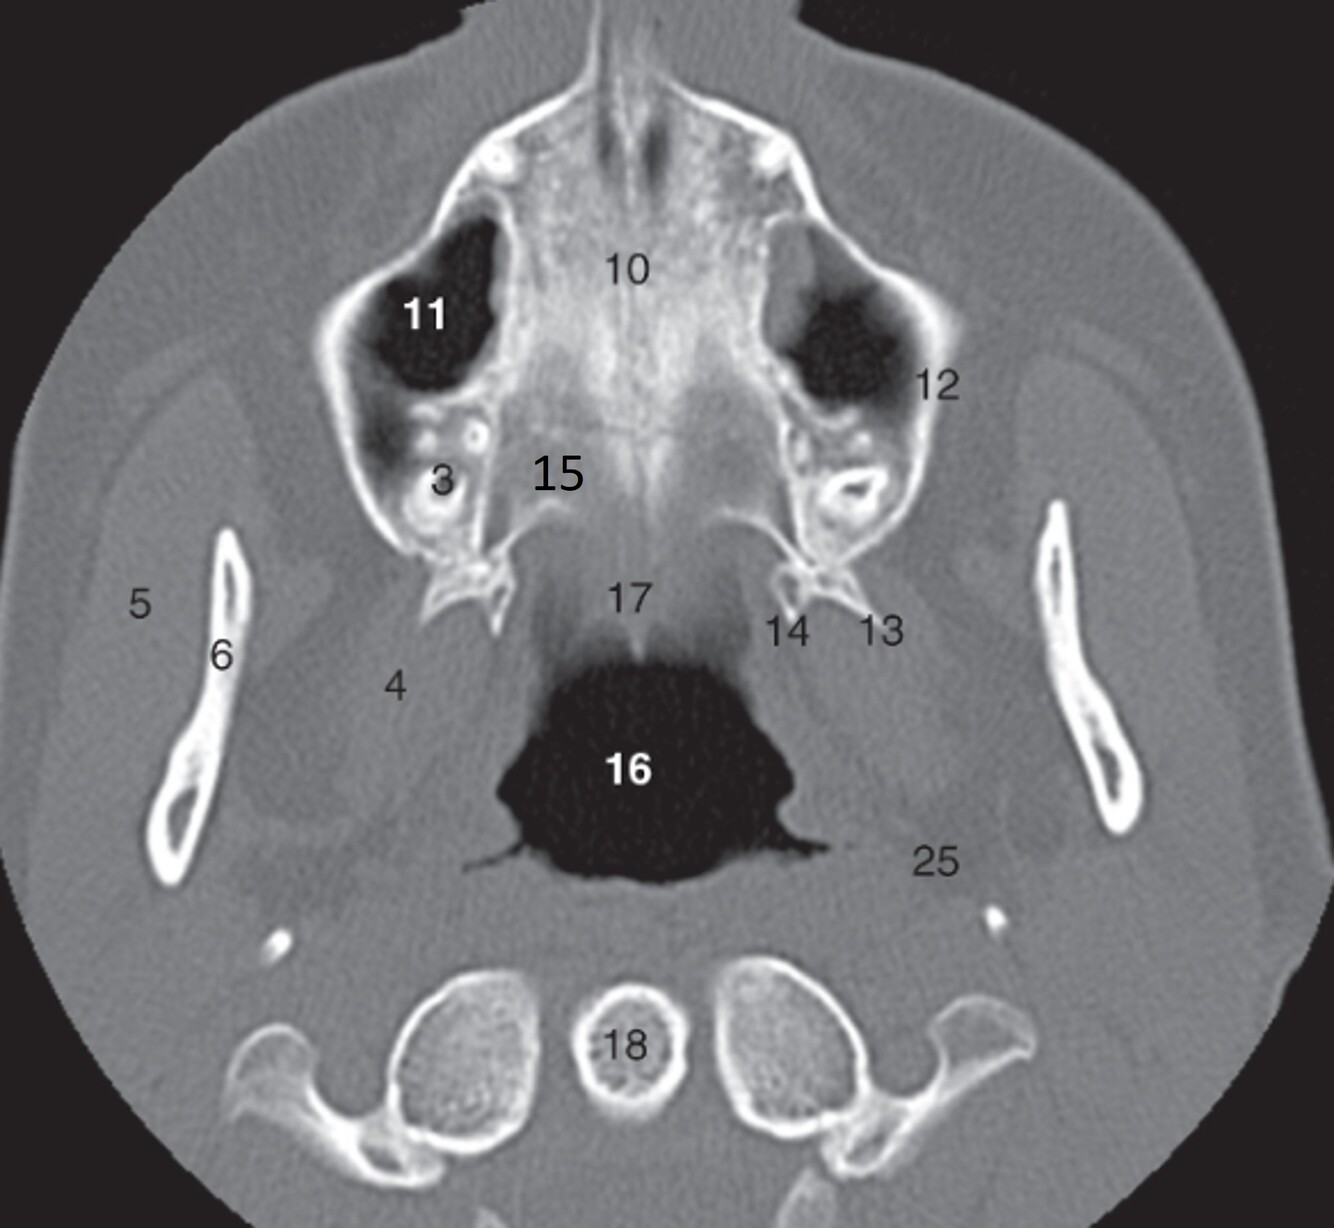

1

Label 5,6,10,11,12

A

5-Rt masseter muscle

6-Rt ramus of mandible

10=Median suture (hard palate)

11=Rt maxillary sinus

12=Rt Maxilla

2

Label 13-18

13=Lt lateral pterygoid process (Sphenoid)

14=Lt. medial pterygoid process (Sphenoid)

15=Horizontal plate (Rt palatine)

16=Nasopharynx

18=Odontoid process of C2

20

Label 36,37,46,62

36=Rt. Inferior nasal concha

37=Lt. Inferior nasal meatus

46=Lt. carotid canal

62= Lt. EAM